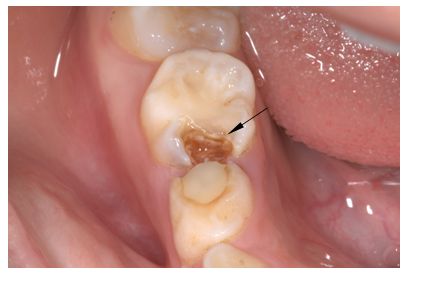

怎样预防龋齿

龋病是口腔常见病、多发病之一,它是在多因素作用下的一种慢性感染性疾病。

圣贝口腔医生任欢表示:防龋工作应从牙齿一萌出就开始。